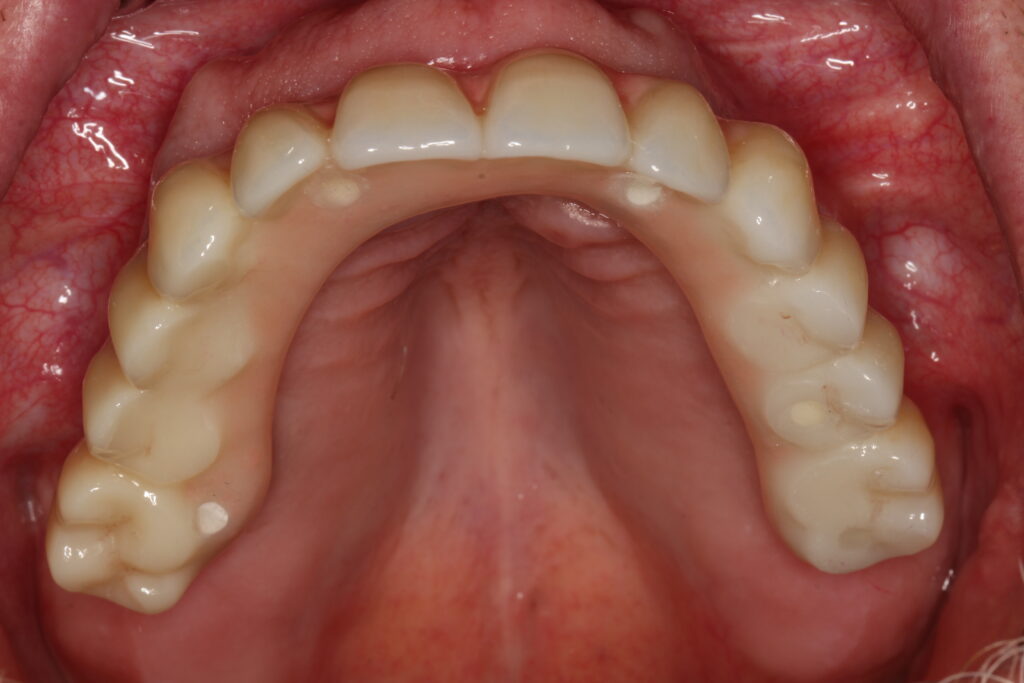

A selection of full arch fixed implant bridge patients after 5 years of wear

Oral Surgeons – Dr Han Choi, Dr Sam Goldsmith, Dr Rajiv Rajpal NSOMS

Prosthodontist – Dr Alan Payne NSOMS/Northland Prosthodontics

Dental technicians – Hosaka Takashi, DT Denture Design, Auckland, CJ Park, Project Dentistry, Auckland and Osteon Medical, Melbourne, Australia.